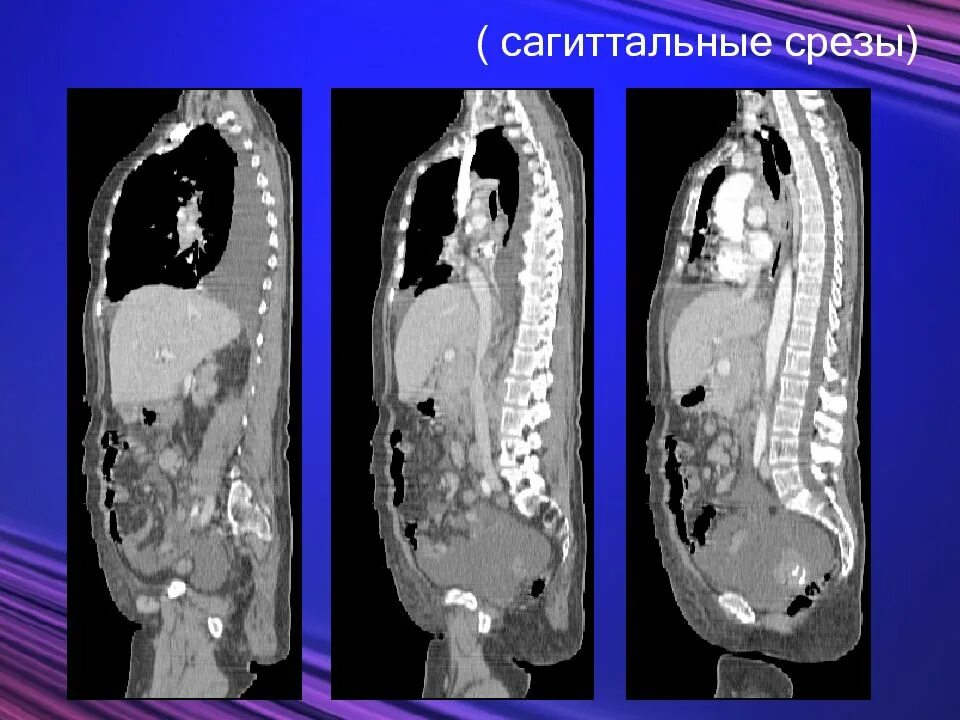

Диагностический срез